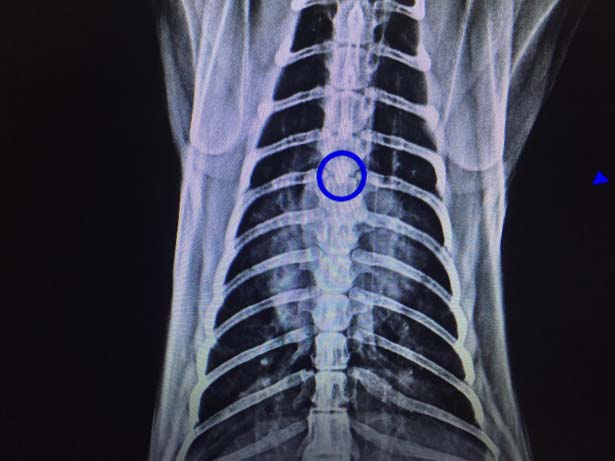

Zonguldak'ta ameliyata alınan kedinin soluk borusundan 1,5 santimlik taş çıkarıldı.

Kastamonu'da hayvanseverlerin baktığı 2 yaşındaki kedi nefes alıp vermekte sorun yaşadı. Ardından hayvanseverler hasta kediyi Kastamonu'da veteriner kliniğine getirdi. Ancak veteriner kliniğinde yeterli ekipman olmadığı için kedi Zonguldak'a nakledildi. Zonguldak Veteriner Kliniğinde röntgeni çekilen kedinin soluk borusunda 1,5 santimlik taş olduğu tespit edildi. Veteriner hekimler Önder Alkan ve Suat Ulucak tarafından 4 saat süren ameliyatla kedinin soluk borusundaki taş çıkarıldı. Yoğun bakıma alınan kedinin durumunun iyi olduğu öğrenildi.

Veteriner Hekim Önder Alkan, ''Dün akşam Kastamonu ilinden geldi bize hastamız. Yaptığımız tetkiklerde soluk borusunda yabancı cisim tespit ettik akciğerin giriş bölgesindeydi kalbin üzerinde kötü bir solunumu vardı boğulmak üzereydi. Açık bir ameliyat geçirdi. Soluk borusundan bir taş çıktı. Zorlu bir ameliyattı 6 saat sürdü. Ameliyattan sonra solunumu düzeldi. Akciğerler düzeldi 3 günlük sıkıntılı bir durumu var. Oynarken muhtemelen oldu aşağıya kadar indi. Bir anda solunum güçlüğünden dolayı anlamış vatandaş ve hemen veterinere getiriyor ve yapılan tetkiklerde yabancı cisim görülüyor. Bu ameliyat için otomatik solumun sistemi gerekiyor. Bu sistem olan yerlerde bu ameliyatlar yapılıyor. Zor ve riskli bir ameliyat” şeklinde konuştu.